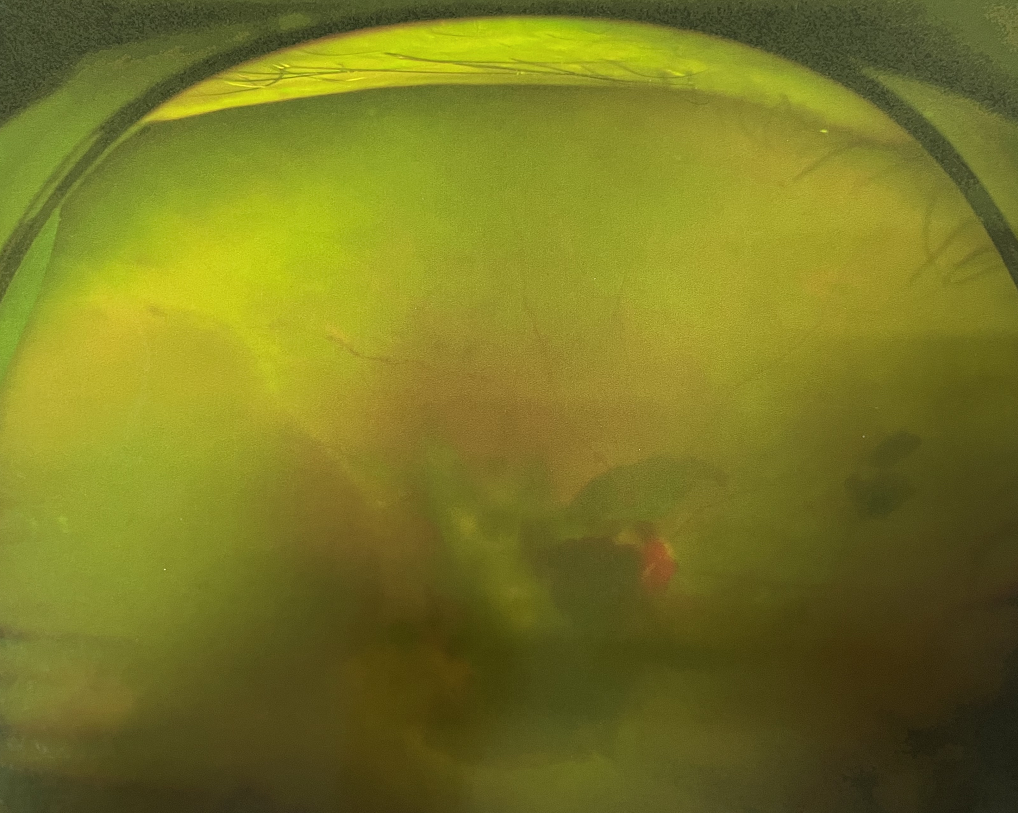

糖尿病視網(wǎng)膜病變是糖尿病在眼部的主要并發(fā)癥,是我國四大致盲眼病之一,主要以視網(wǎng)膜血管改變?yōu)椴±硖卣?。眼底多表現(xiàn)為視網(wǎng)膜出血、滲出、新生血管及增殖膜形成,嚴(yán)重威脅患者的視覺健康。

糖尿病視網(wǎng)膜病變

糖尿病視網(wǎng)膜病變可分為六期:

?、衿冢河形⒀芰龌虿⒂行〕鲅c(diǎn)。

?、蚱冢河悬S白色“硬性滲出”或并有出血斑。

?、笃冢河邪咨?ldquo;軟性滲出”或并有出血斑。

?、羝冢貉鄣子行律芑虿⒂胁Aw積血。

?、跗冢貉鄣子行律芑虿⒂欣w維膜增生。

?、銎冢貉鄣子行律芑虿⒂欣w維膜增生,并發(fā)視網(wǎng)膜脫離。